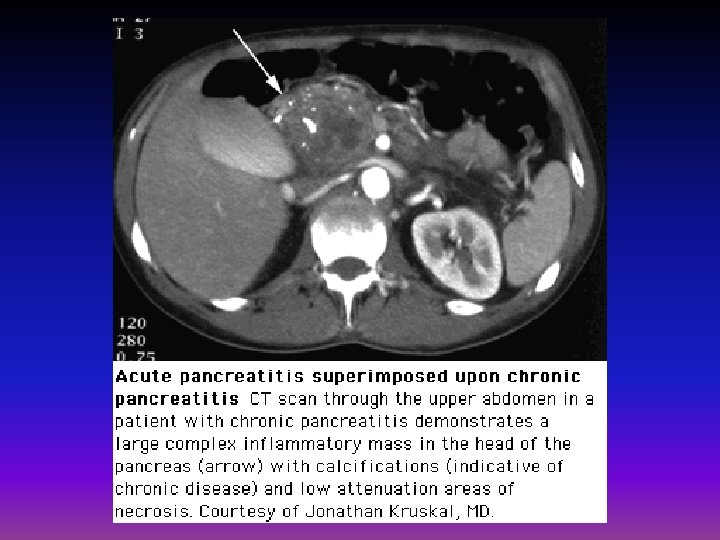

• Transabdominal US: No gallstones or mass in head of pancreas • CT scan: The extrahepatic bile duct was mildly dilated and "generous pancreas" was noted but there was no mass.

CT, MRI, US • • calcifications ductal dilatation enlargement of the pancreas fluid collections (eg, pseudocysts)

Complications • • pseudocyst formation bile duct or duodenal obstruction pancreatic ascites or pleural effusion splenic vein thrombosis Pseudoaneurysms pancreatic cancer acute attacks of pancreatitis( particularly alcoholics who continue drinking)